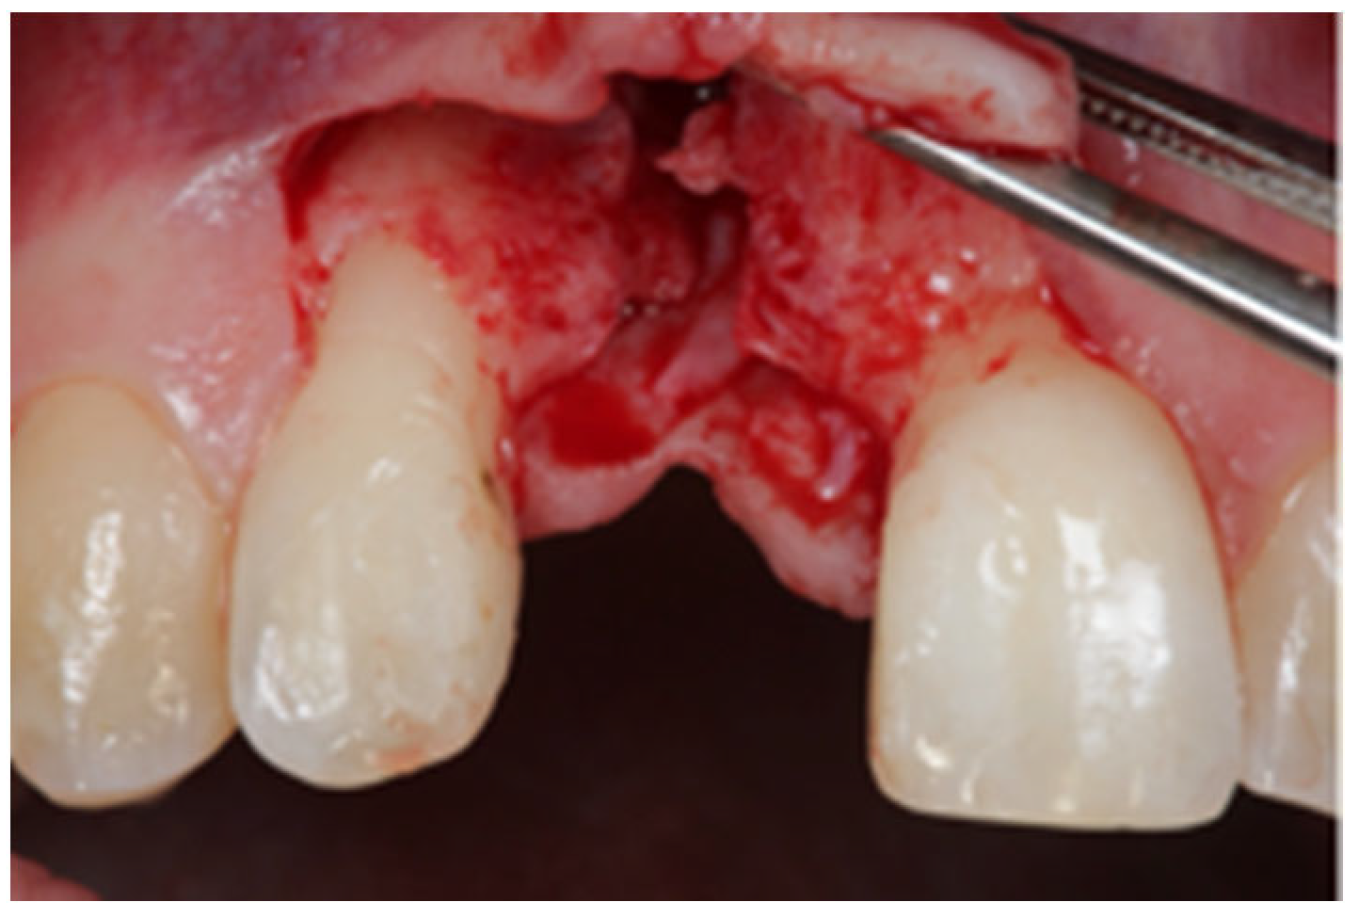

2.1. Surgical Technique